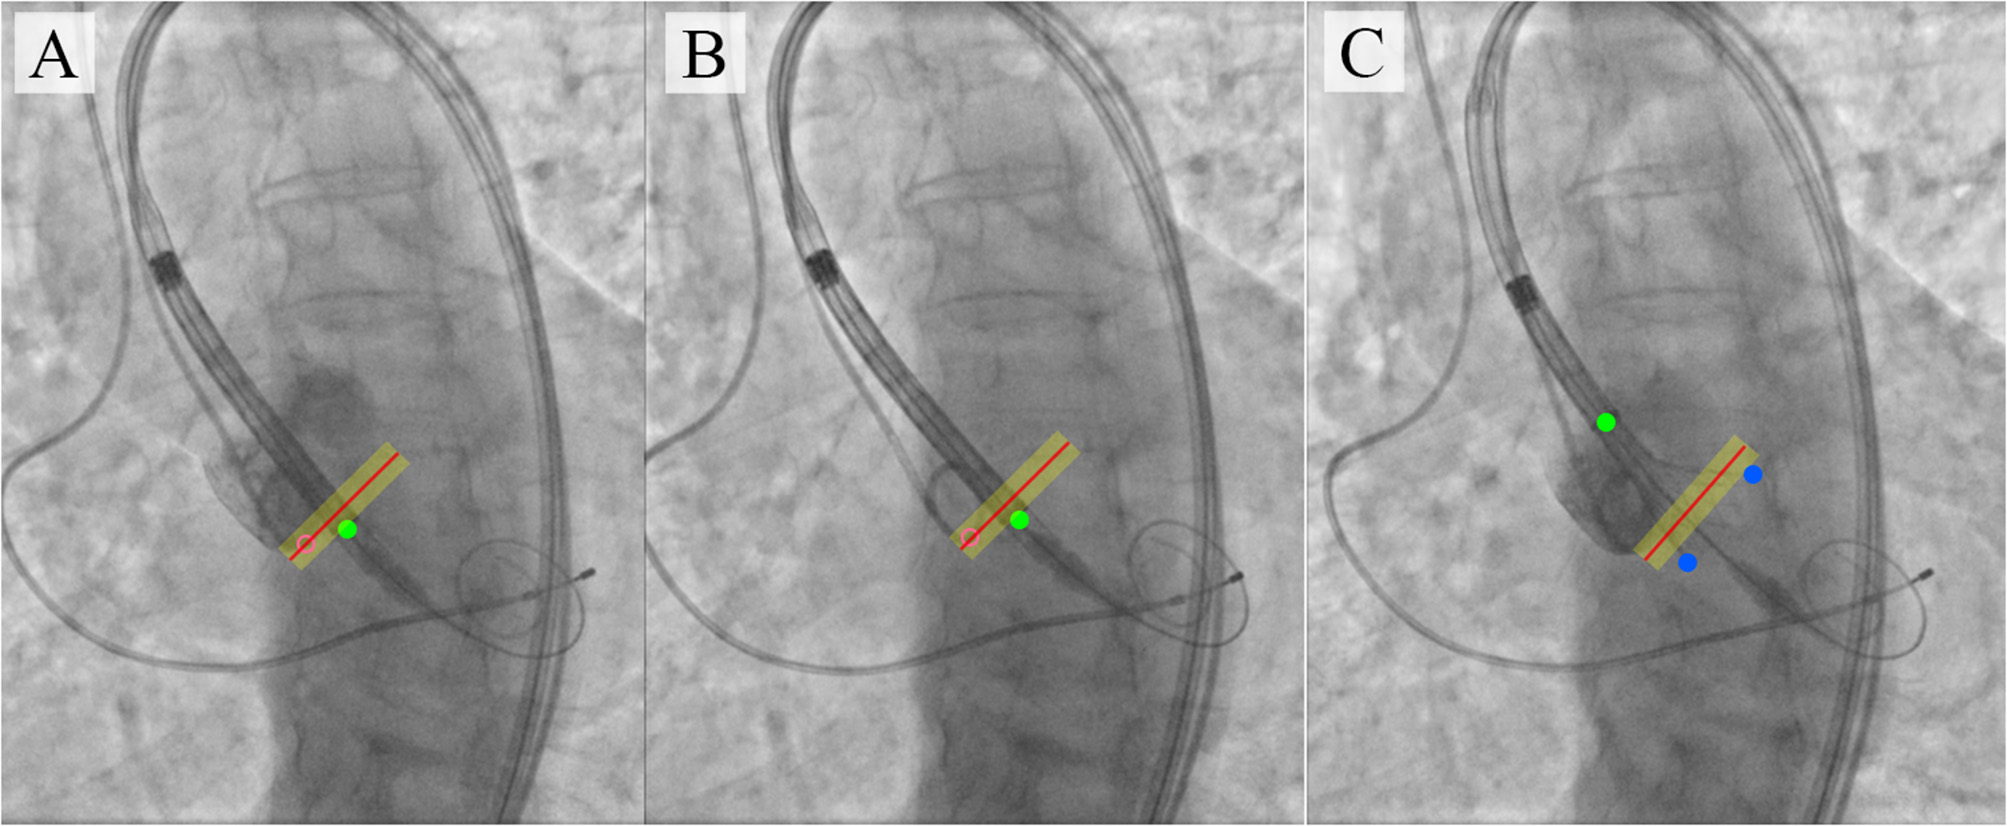

During the TAVI, we collected 35 video series of 1,000 × 1,000 pixels with an 8-bit depth (a scale from 0 to 255). The final sample consisted of 3,730 grayscale images, of which 2,984 (80%) images were used as the training set and 746 (20%) images were used as the validation set. TAVI allowed obtaining a series of anonymized images illustrating three essential steps: positioning of the catheter and delivery system (Figure 2A); beginning of the capsule retraction and exposing the prosthesis (Figure 2B); deployment of the prosthesis (Figure 2C). The maximum of 11 keypoints of interest (from 1 to 11 over each image) was labeled and annotated (Figures 2D–H). A brief description of the keypoints is provided below.

Figure 2

Algorithm for labeling intraoperative aortography images and defining the keypoints for the TAVI tracking system. (A) represents the positioning of the delivery system; (B) represents the transcatheter aortic valve deployment and the actuator rotation; (C) highlights the 1/3 of the valve deployment; (D) shows the labeling of the keypoints on the catheter; (E) shows the labeling of the keypoints indicative of the aortic root; (F) shows the labeling of the keypoints on the valve stent at the stage of its 1/3 deployment; (G) is a visualization of the keypoints on the distal part of the delivery system according to the segmented aortograms; (H) is a 3D model of the target aortic valve structure.